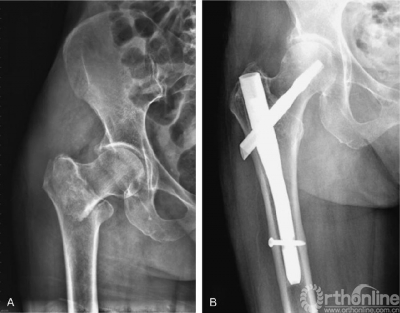

图1 A,右髋正位片显示AO分型31-A12型骨折;B,右髋正位片显示短款股骨近端髓内钉固定术后,骨折完全愈合。